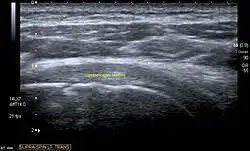

Longitudinal ultra sonography of the supraspinatus tendon

Transversal ultra sonography of the supraspinatus tendon